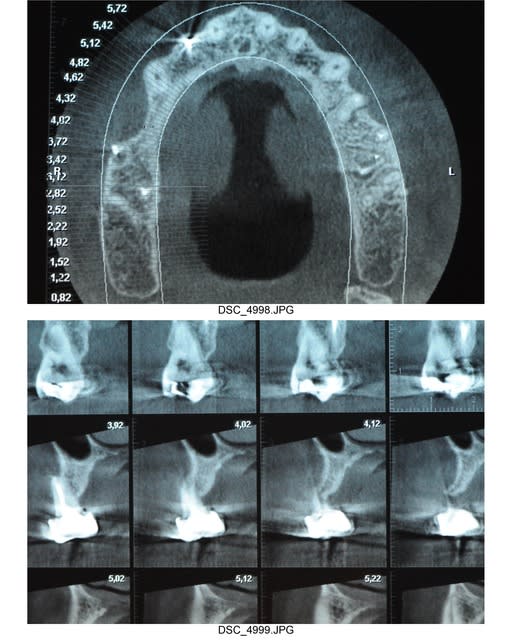

pourquoi pas , mais je ne suis pas convaincu qu'une ingression (si c'est ce à quoi tu penses) sur 16 et17 soit encore possible.

la limite osseuse dans ces zones vient déjà en compétition avec la courbe occusale idéale. non ?

Dans ce cas ci, après extractions de 16 et 17, une simple ostéotoplastie (mais conséquente quand même!) va suffire à récupérer une courbe occlusale convenable. on a ici la chance d'avoir une hauteur sinuso-dental importante.

avec cette méthode, on récupère beaucoup d'os et on a pas de problèmes pour suturer les berges entre elles du fait de l'ostéotomie.

je n'ai pas pu mettre d'implants en situation 14 et 15 à cause de la concavité énorme qu'il y avait.

donc reconstruction osseuse avec membrane titane et en dessous tous l'os que j'avais récupéré de l'ostéoplastie.

si ça marche pas, ce sera greffe d'apposition.